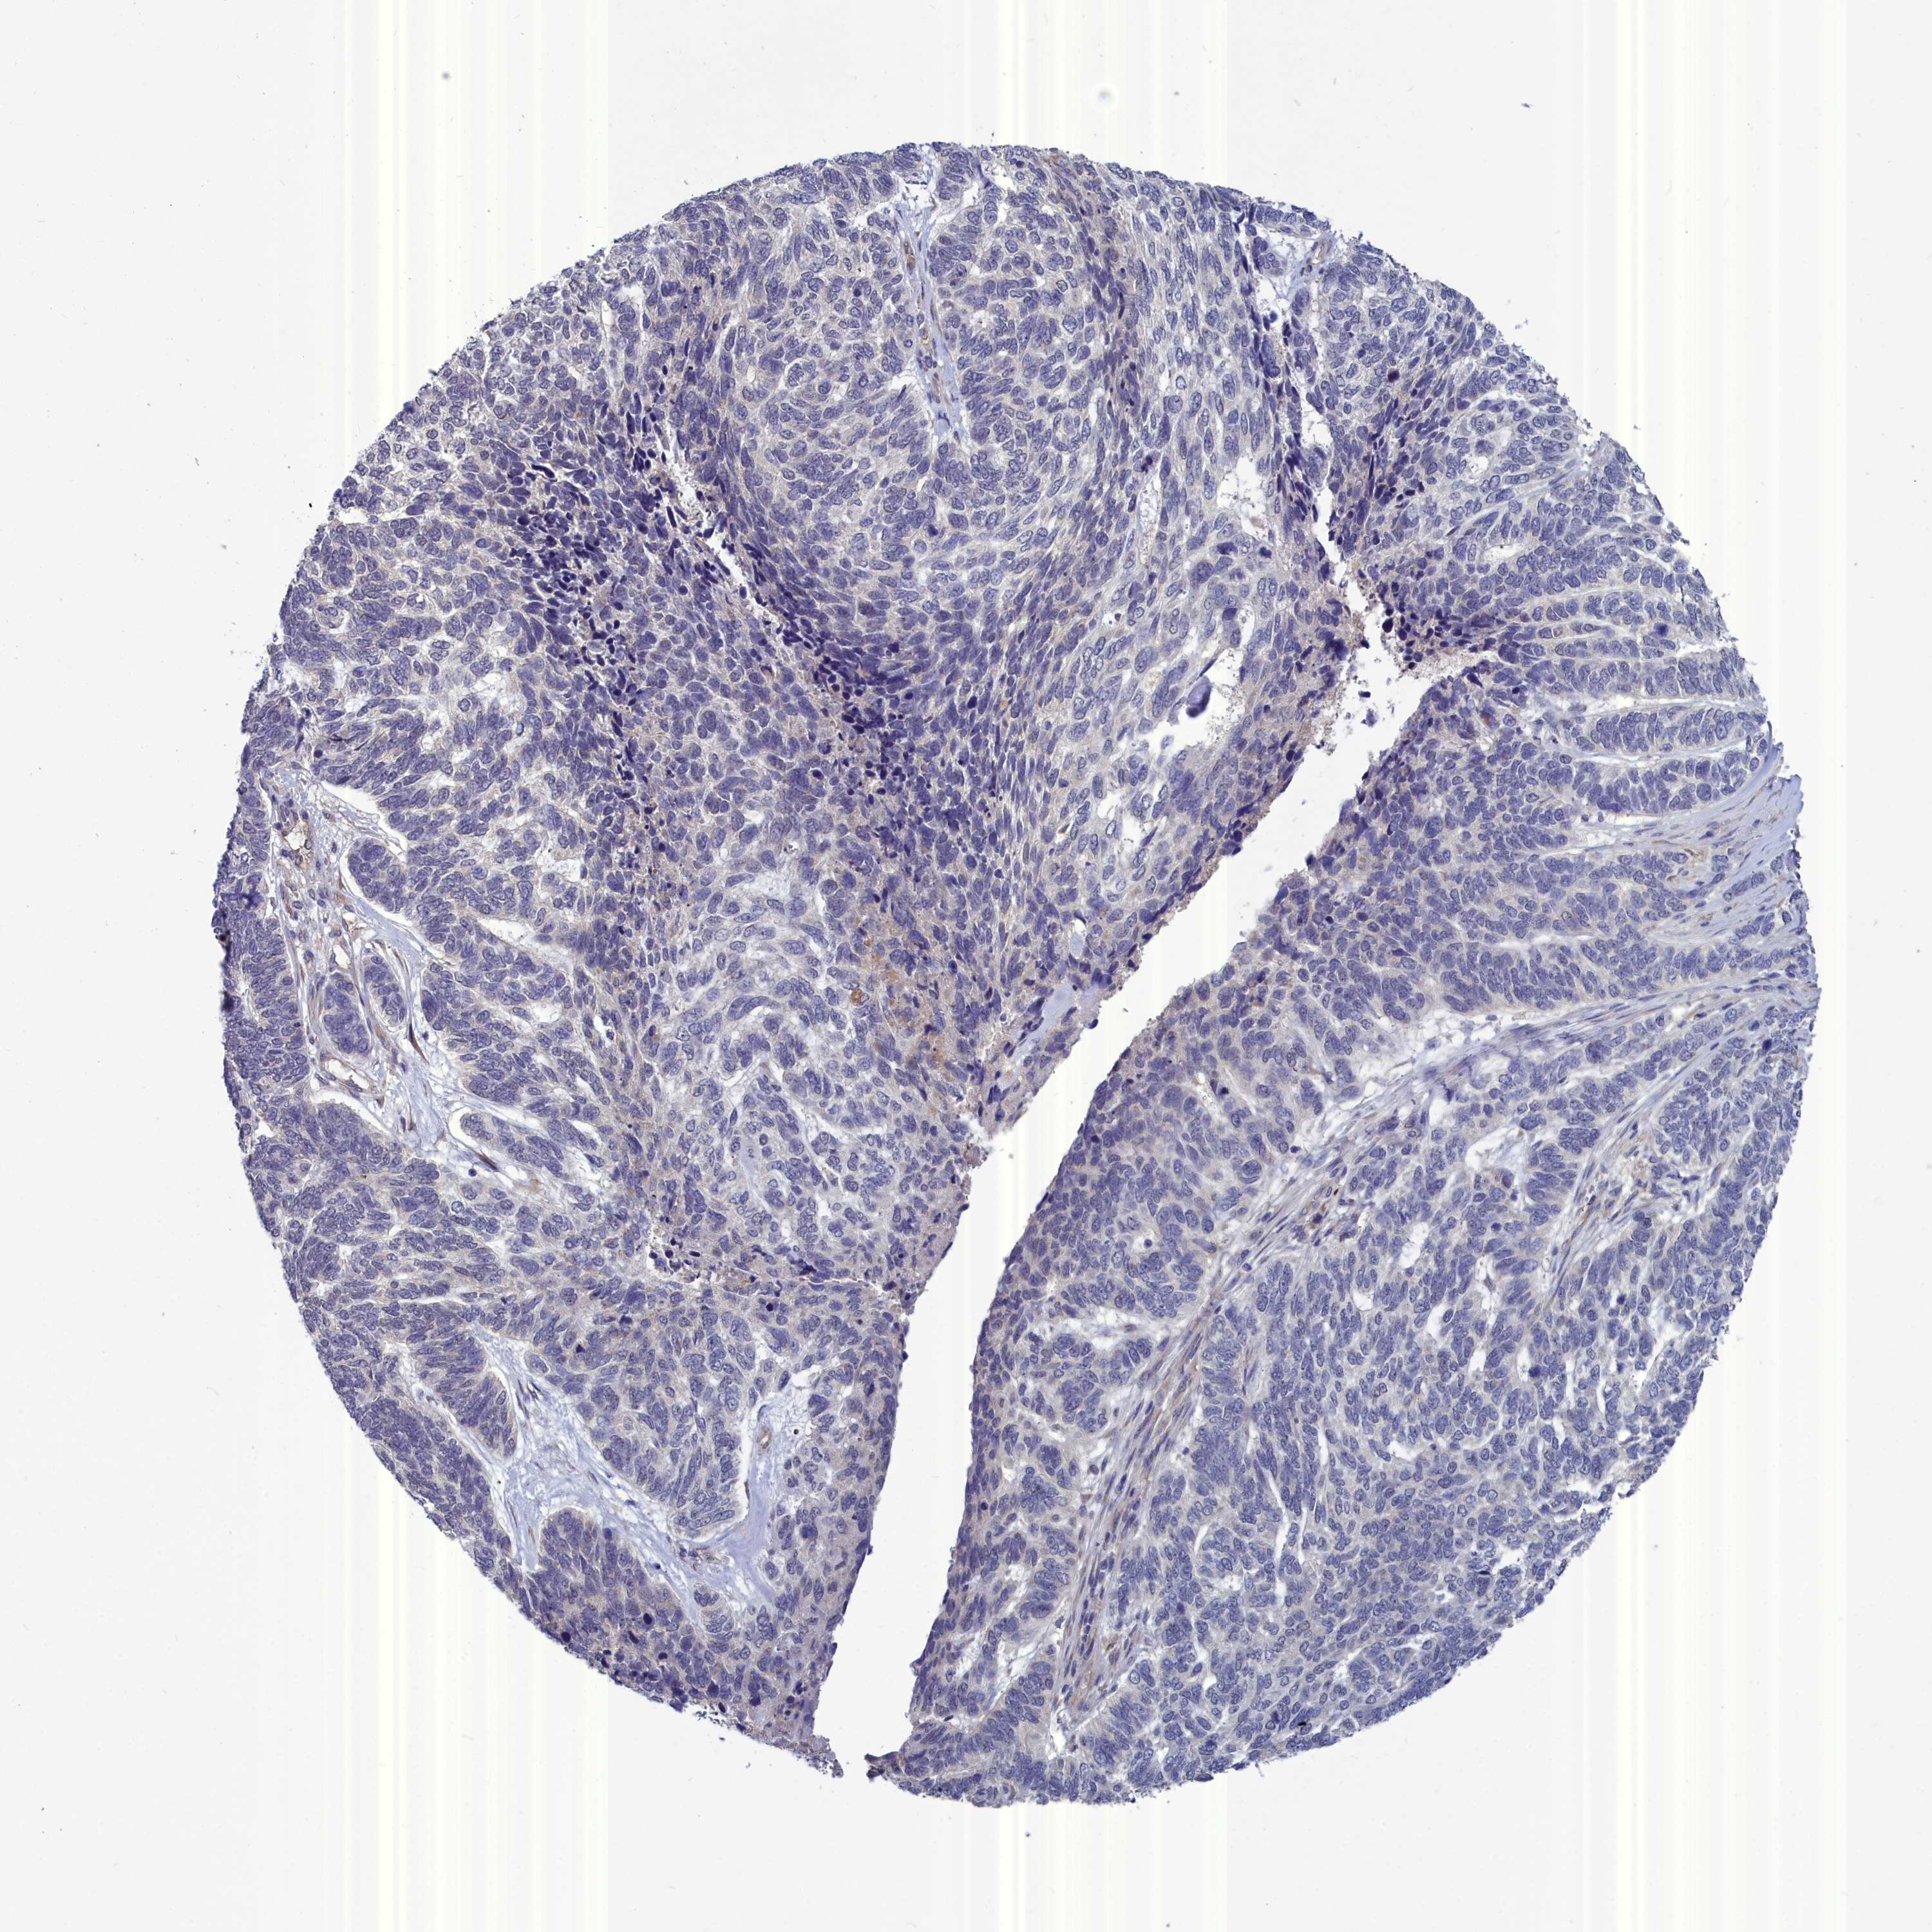

SKIN CANCER - Protein expressioni

A mouse-over function shows sample information and annotation data. Click on an image to view it in a full screen mode. Samples can be filtered based on level of antibody staining by selecting one or several of the following categories: high, medium, low and not detected. The assay and annotation is described here.

Each image is clickable and will lead to virtual microscopy that enables deeper exploration of all samples and also displays staining intensity scores, fraction scores and subcellular localization as well as patient and tissue information for each sample.

Antibody HPA000263

Staining

High

Medium

Low

Not detected

Intensity

Strong

Moderate

Weak

Negative

Quantity

>75%

75%-25%

<25%

None

Location

Nuclear

Cytoplasmic/membranous

Cytoplasmic/membranous,nuclear

Squamous cell carcinoma, NOS